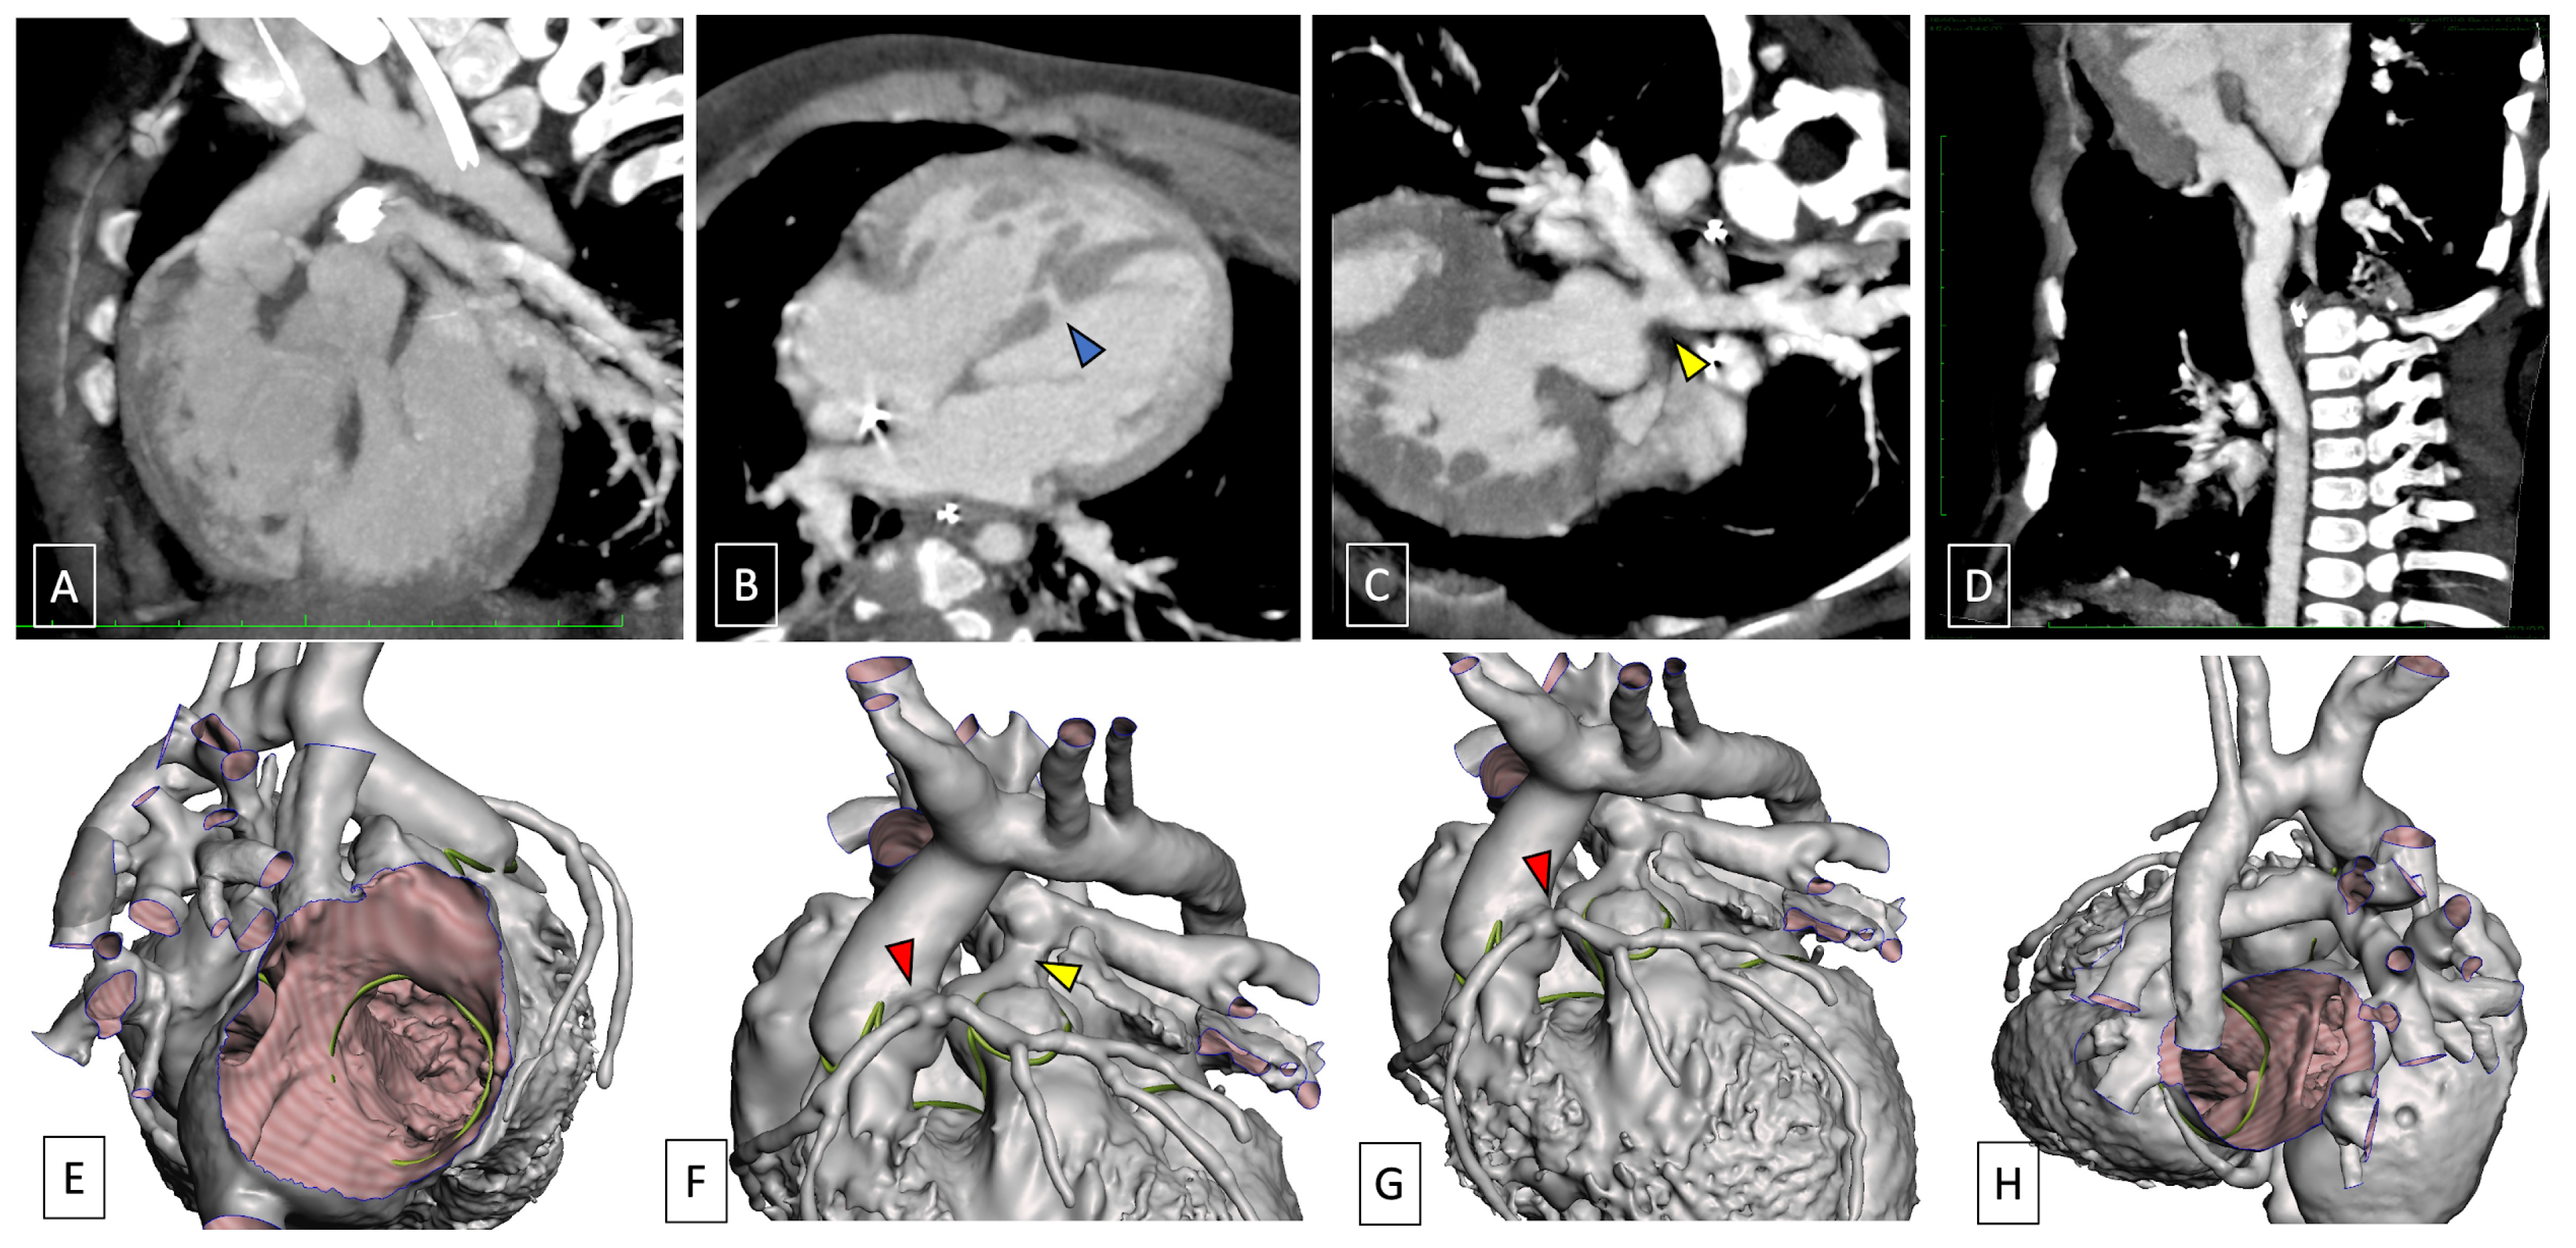

- Kumar, P.; Bhatia, M. Role of CT in the Pre- and Postoperative Assessment of Conotruncal Anomalies. Radiol. Cardiothorac. Imaging 2022, 4, e210089. [Google Scholar] [CrossRef] [PubMed]

- Swanson, S.K.; Sayyouh, M.M.; Bardo, D.M.E.; Ghadimi Mahani, M.; Lu, J.C.; Dorfman, A.L.; Agarwal, P.P. Interpretation and Reporting of Coronary Arteries in Transposition of the Great Arteries: Cross-Sectional Imaging Perspective. J. Thorac. Imaging 2018, 33, W14–W21. [Google Scholar] [CrossRef] [PubMed]

- Pergola, V.; Avesani, M.; Reffo, E.; Da Pozzo, S.; Cavaliere, A.; Padalino, M.; Vida, V.; Motta, R.; Di Salvo, G. Unveiling the gothic aortic arch and cardiac mechanics: Insights from young patients after arterial switch operation for d-transposition of the great arteries. Monaldi Arch. Chest Dis. 2023, 94, 2712. [Google Scholar] [CrossRef] [PubMed]